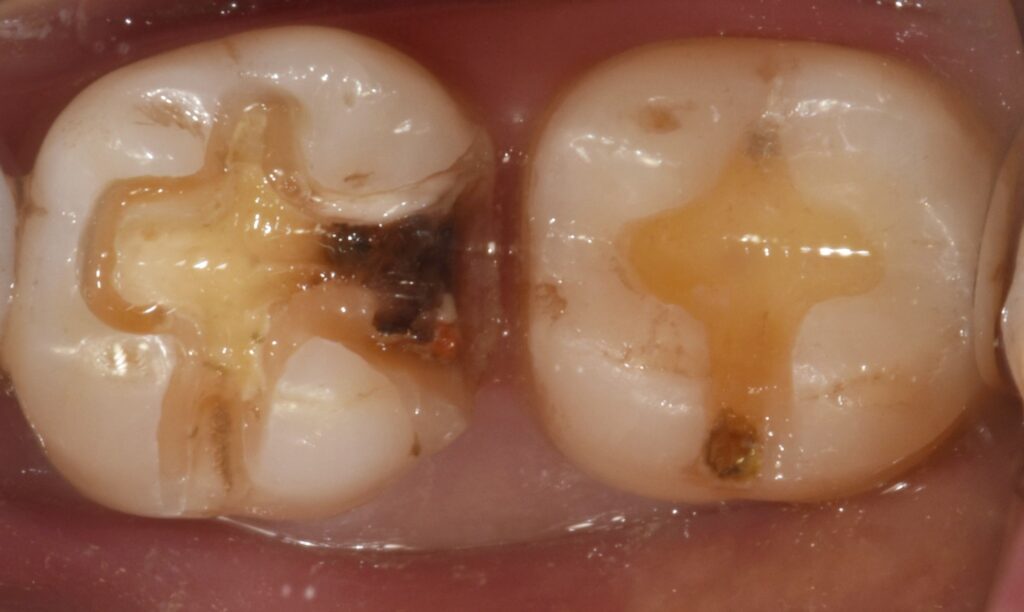

만약 육안으로만 진단을 해서 위와 같은 상태를 바로 잡지 않는 다면 어떻게 될까요?

이차우식

이런식으로 2차 충치가 깊게 생길 가능성이 매우 높습니다.

충치가 깊게 진행 될 경우 신경치료와 크라운 치료가 동반되어야 합니다.

치료에 소요되는 시간과 고통 비용이 모두 상당히 올라가게 되죠.